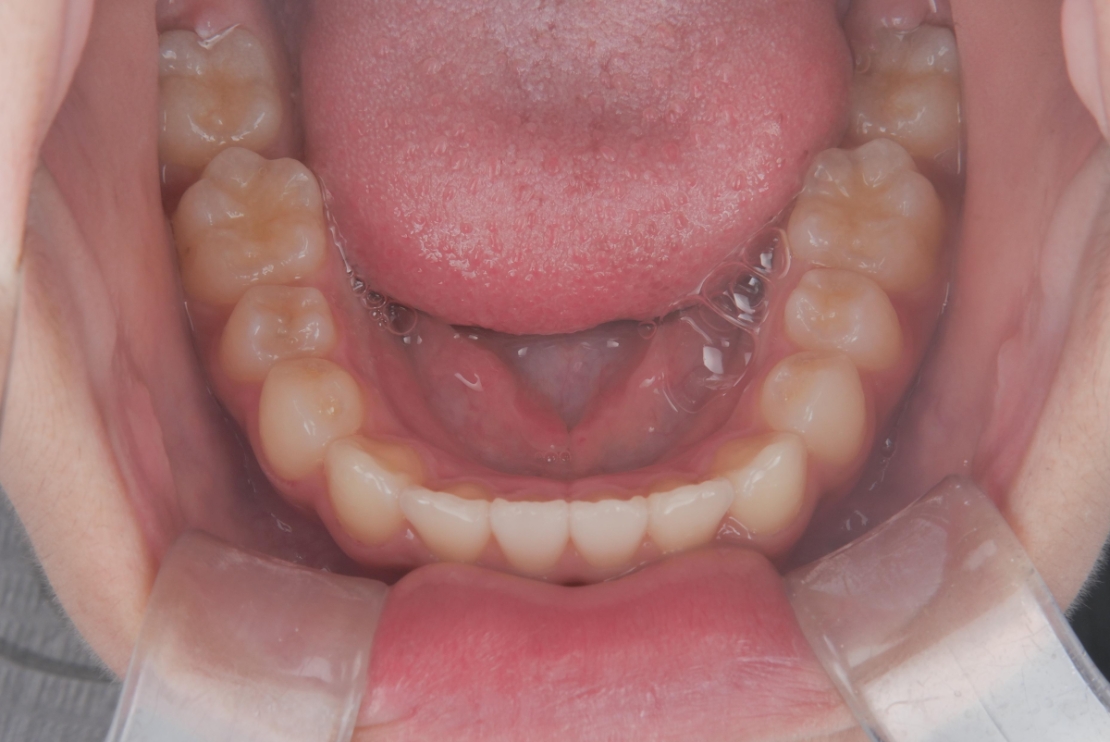

BEFORE

スタート時9歳の患者さまで、主訴は上下前歯のガタつきでした。早期に歯並びを整えたいとの思いからご相談に来院されました。

成長期であることを踏まえ、段階的な治療計画を立てました。まずプレオルソを1年1ヶ月使用し、口腔周囲筋や歯列のバランスを整えたうえで、その後、マウスピース矯正インビザライン・ファーストにて矯正治療を行い、さらに1年8ヶ月かけて歯並びを整えています。

治療期間は合計2年9ヶ月で、上下前歯のガタつきは改善し、見た目と機能の両面が整った歯列へと改善しました。